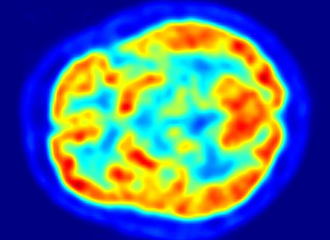

健康脑部的氟代脱氧葡萄糖正子断层扫描。热区表示葡萄糖摄取量较高,基底核的状况能帮助诊断帕金森病。